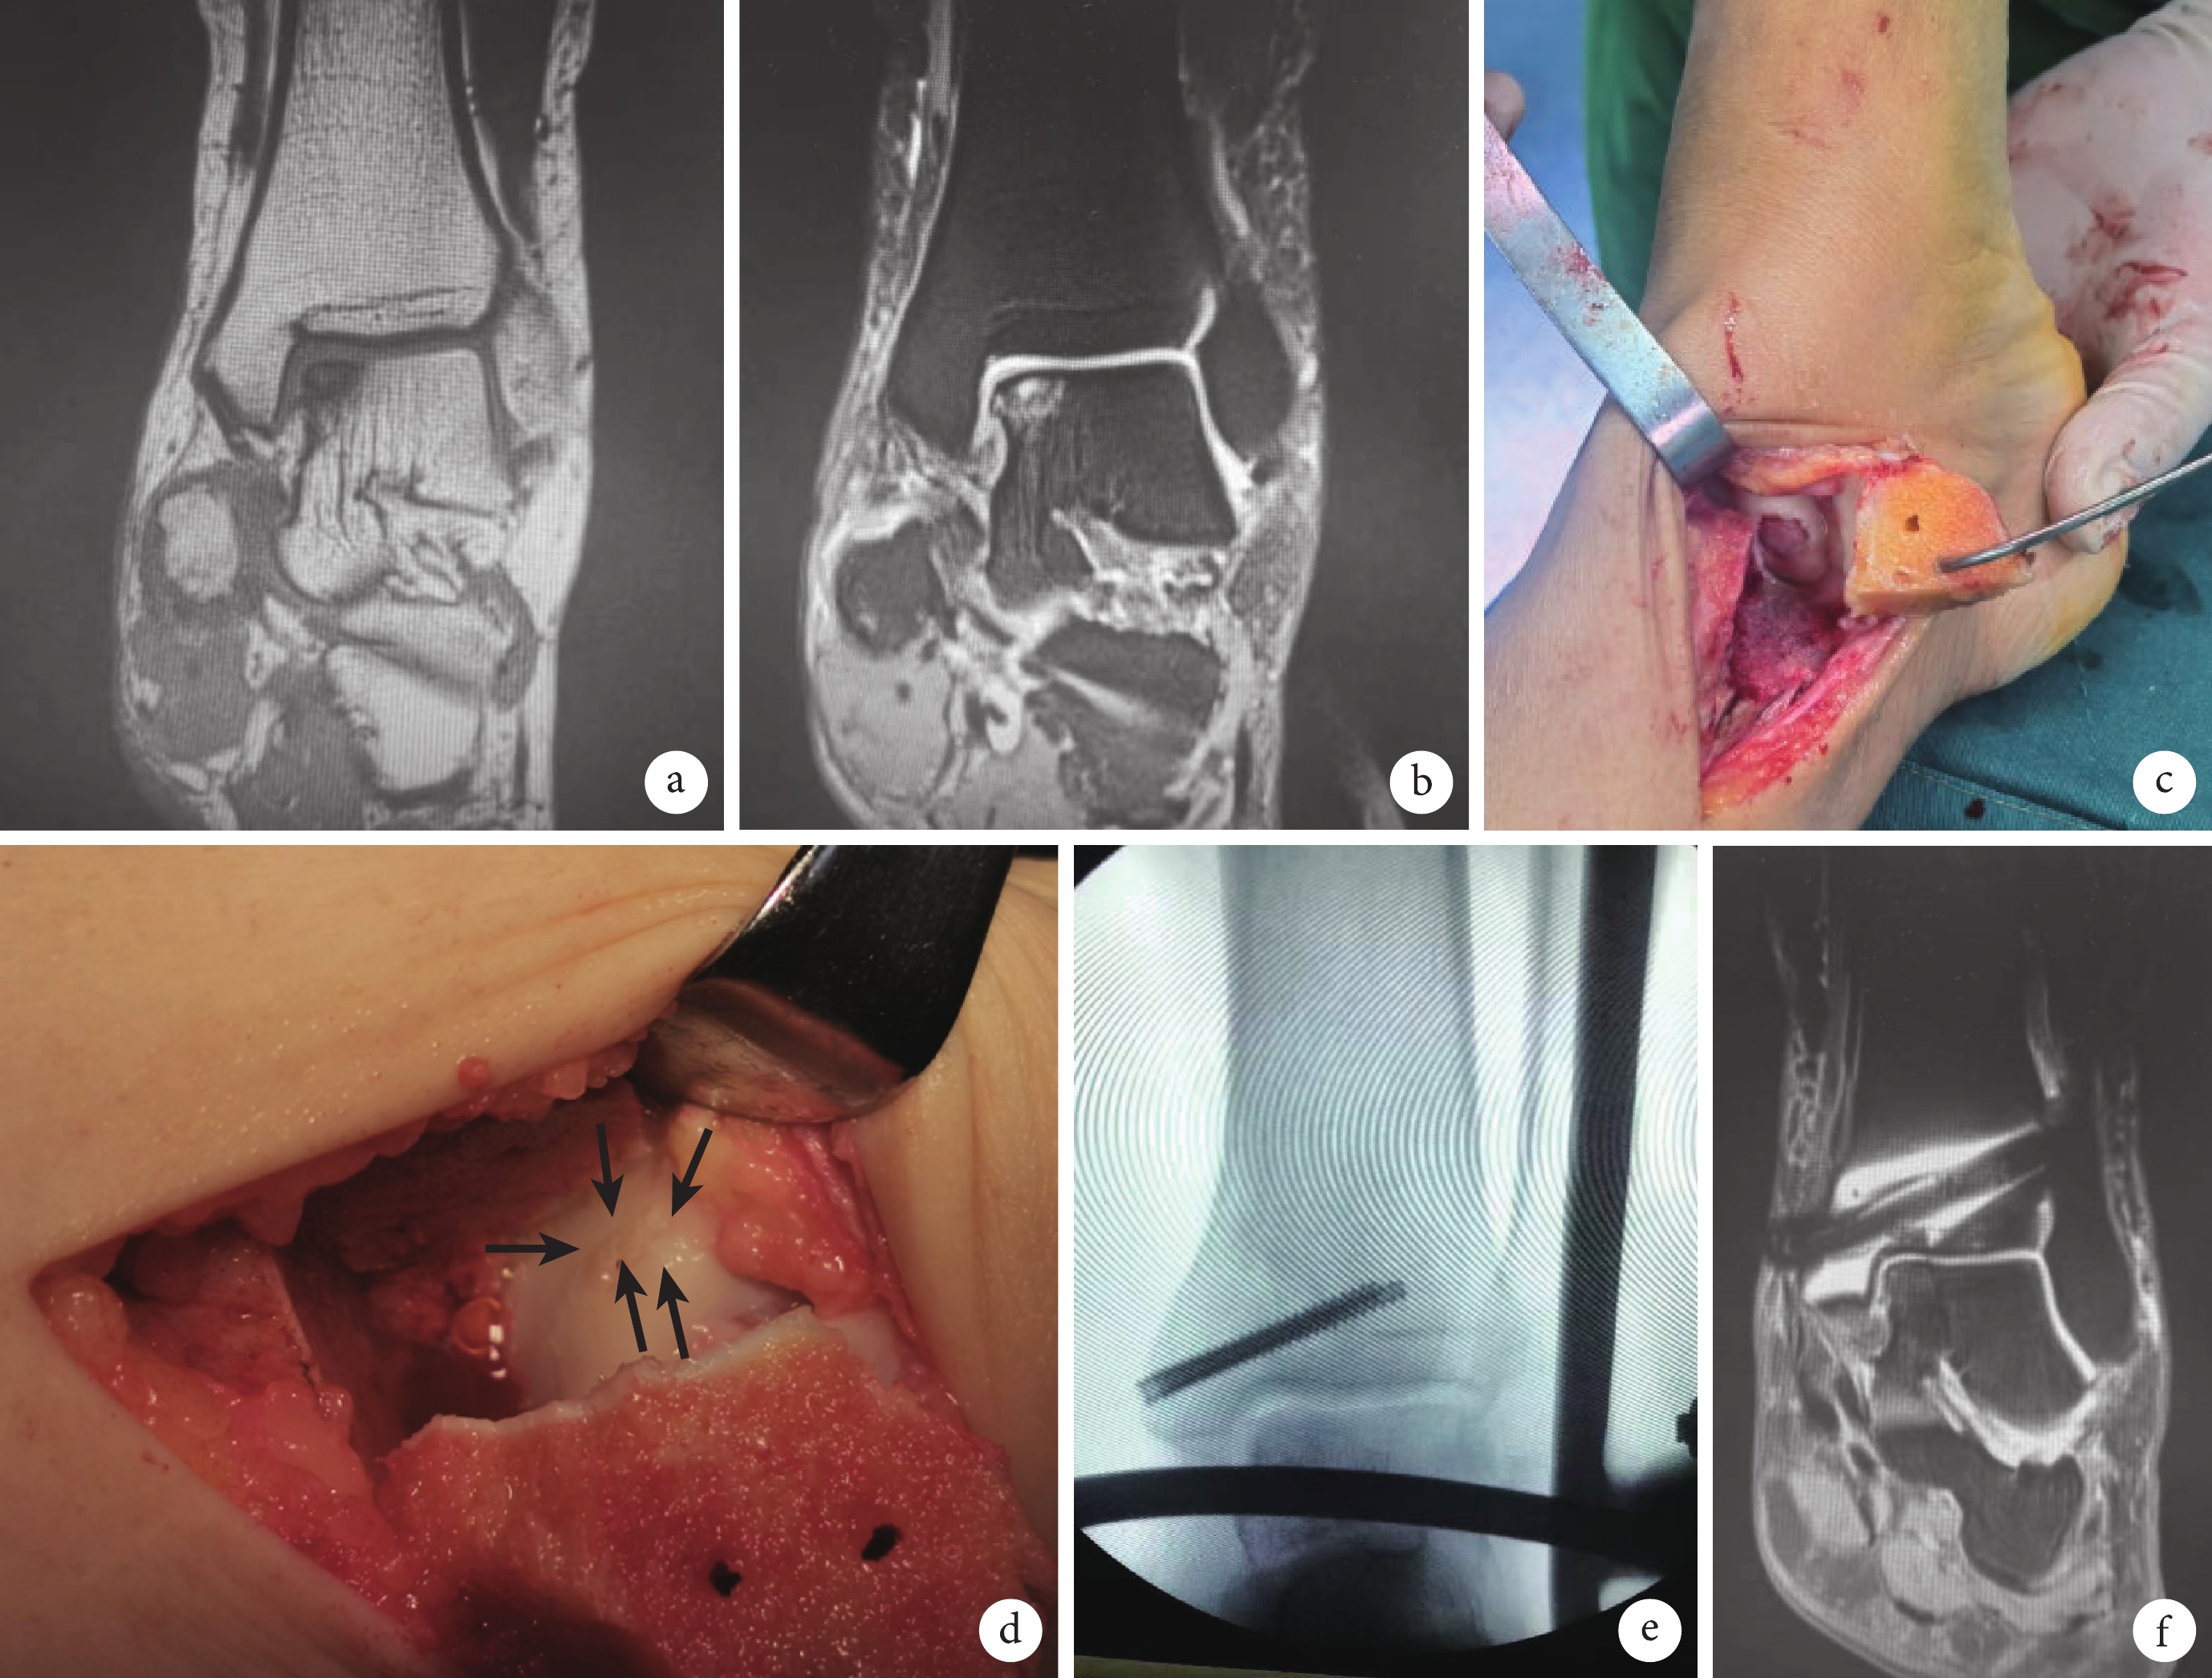

術后 1 年隨訪時,患者 MRI 顯示距骨軟骨損傷變性范圍和深度較術前明顯減小,見表2。隨訪 MRI 見患側關節面無臺階、無骨質缺損。典型病例見圖1。

a. 術前 MRI-T1 顯示距骨內側距骨損傷區;b. 術前 MRI-T2 顯示距骨損傷伴水腫;c. 術中彩色像,內踝截骨顯露損傷軟骨;d. 術中彩色像,清理損傷區后植入骨柱,黑箭示植入的骨軟骨;e. 術中 C 臂透視確認外固定支架維持踝關節間隙;f. 術后 6 個月隨訪 MRI 示距骨軟骨范圍明顯縮小。患者,女,48 歲,術前診斷為左距骨軟骨損傷